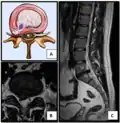

- Click images to see larger versions

-

Lumbar disc lesions, classification -

Normal situation and spinal disc herniation in cervical vertebrae -

Illustration depicting herniated disc and spinal nerve compression -

Nucleus herniating through tear in annulus (with MRI)[9] -

Illustration showing disc degeneration, prolapse, extrusion and sequestration

- Magnetic resonance imaging is the gold standard study for confirming a suspected LDH. With a diagnostic accuracy of 97%, it is the most sensitive study to visualize a herniated disc due to its significant ability in soft tissue visualization. MRI also has higher inter-observer reliability than other imaging modalities. It suggests disc herniation when it shows an increased T2-weighted signal at the posterior 10% of the disc. Degenerative disc diseases have shown a correlation with Modic type 1 changes. When evaluating for postoperative lumbar radiculopathies, the recommendation is that the MRI is performed with contrast unless otherwise contraindicated. MRI is more effective than CT in distinguishing inflammatory, malignant, or inflammatory etiologies of LDH. It is indicated relatively early in the course of evaluation (<8 weeks) when the patient presents with relative indications like significant pain, neurological motor deficits, and cauda equina syndrome. Diffusion tensor imaging is a type of MRI sequence used for detecting microstructural changes in the nerve root. It may be beneficial in understanding the changes that occur after herniated lumbar disc compresses a nerve root, and might help in differentiating the patients that need surgical intervention. In patients with a high suspicion of radiculopathy due to lumbar disc herniation, yet the MRI is equivocal or negative, nerve conduction studies are indicated.[44] T2-weighted images allow for clear visualization of protruded disc material in the spinal canal.

MRI scan of cervical disc herniation between C5 and C6 vertebrae -

MRI scan of cervical disc herniation between C6 and C7 vertebrae -

MRI scan of large herniation (on the right) of the disc between L4 and L5 vertebrae -

A rather severe herniation of the L4–L5 disc -

Example of a herniated disc at L5–S1 in the lumbar spine